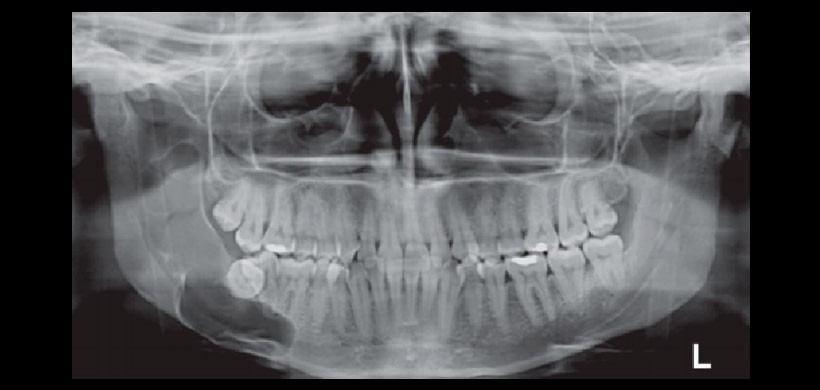

Figura 1: (A) Radiografía panorámica de un TOQ que se presenta como una gran radiolucidez multilocular con desplazamiento de piezas dentales y afección de maxilar inferior. Fuente: Srivatsan 2014. (B) Corte axial de un CBCT que muestra la extensión de la lesión producida por un TOQ. (Fuente: Alatorre 2014)

Figura 4: OPG de la lesión a los 11 meses (evolución muy positiva)